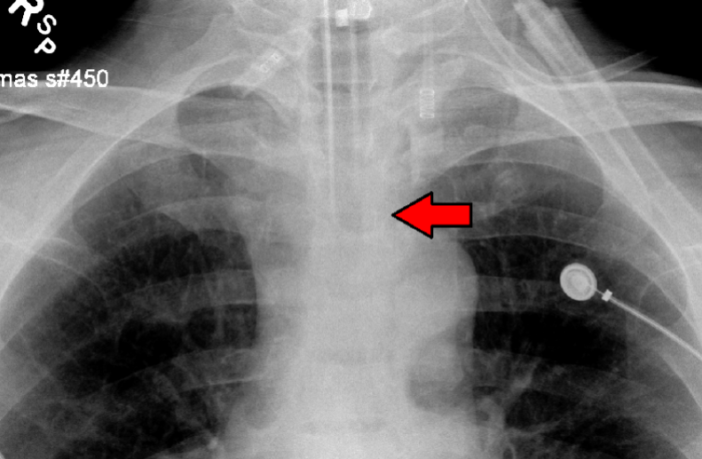

Preview Image: Intubation Tube in Position